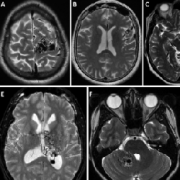

颅内动静脉畸形的诊断和评估,显微外科切除仍然是仔细选择的动静脉畸形的优选治疗方法,因为它可以立即明确地排除AVM。为此,已有许多AVM分类体系被...

脑动静脉畸形手术的现代分类及预后评估 (Modern classification and outcome predictors of surgery in patients with brain arteriovenous malformations) 英文摘要: Brain arterioveno...

功能区亚型是否影响 动静脉畸形手术 的预后? (Does eloquence subtype influence outcome following arteriovenous malformation surgery?) 英文简介: OBJECTIVE Although numerous art...